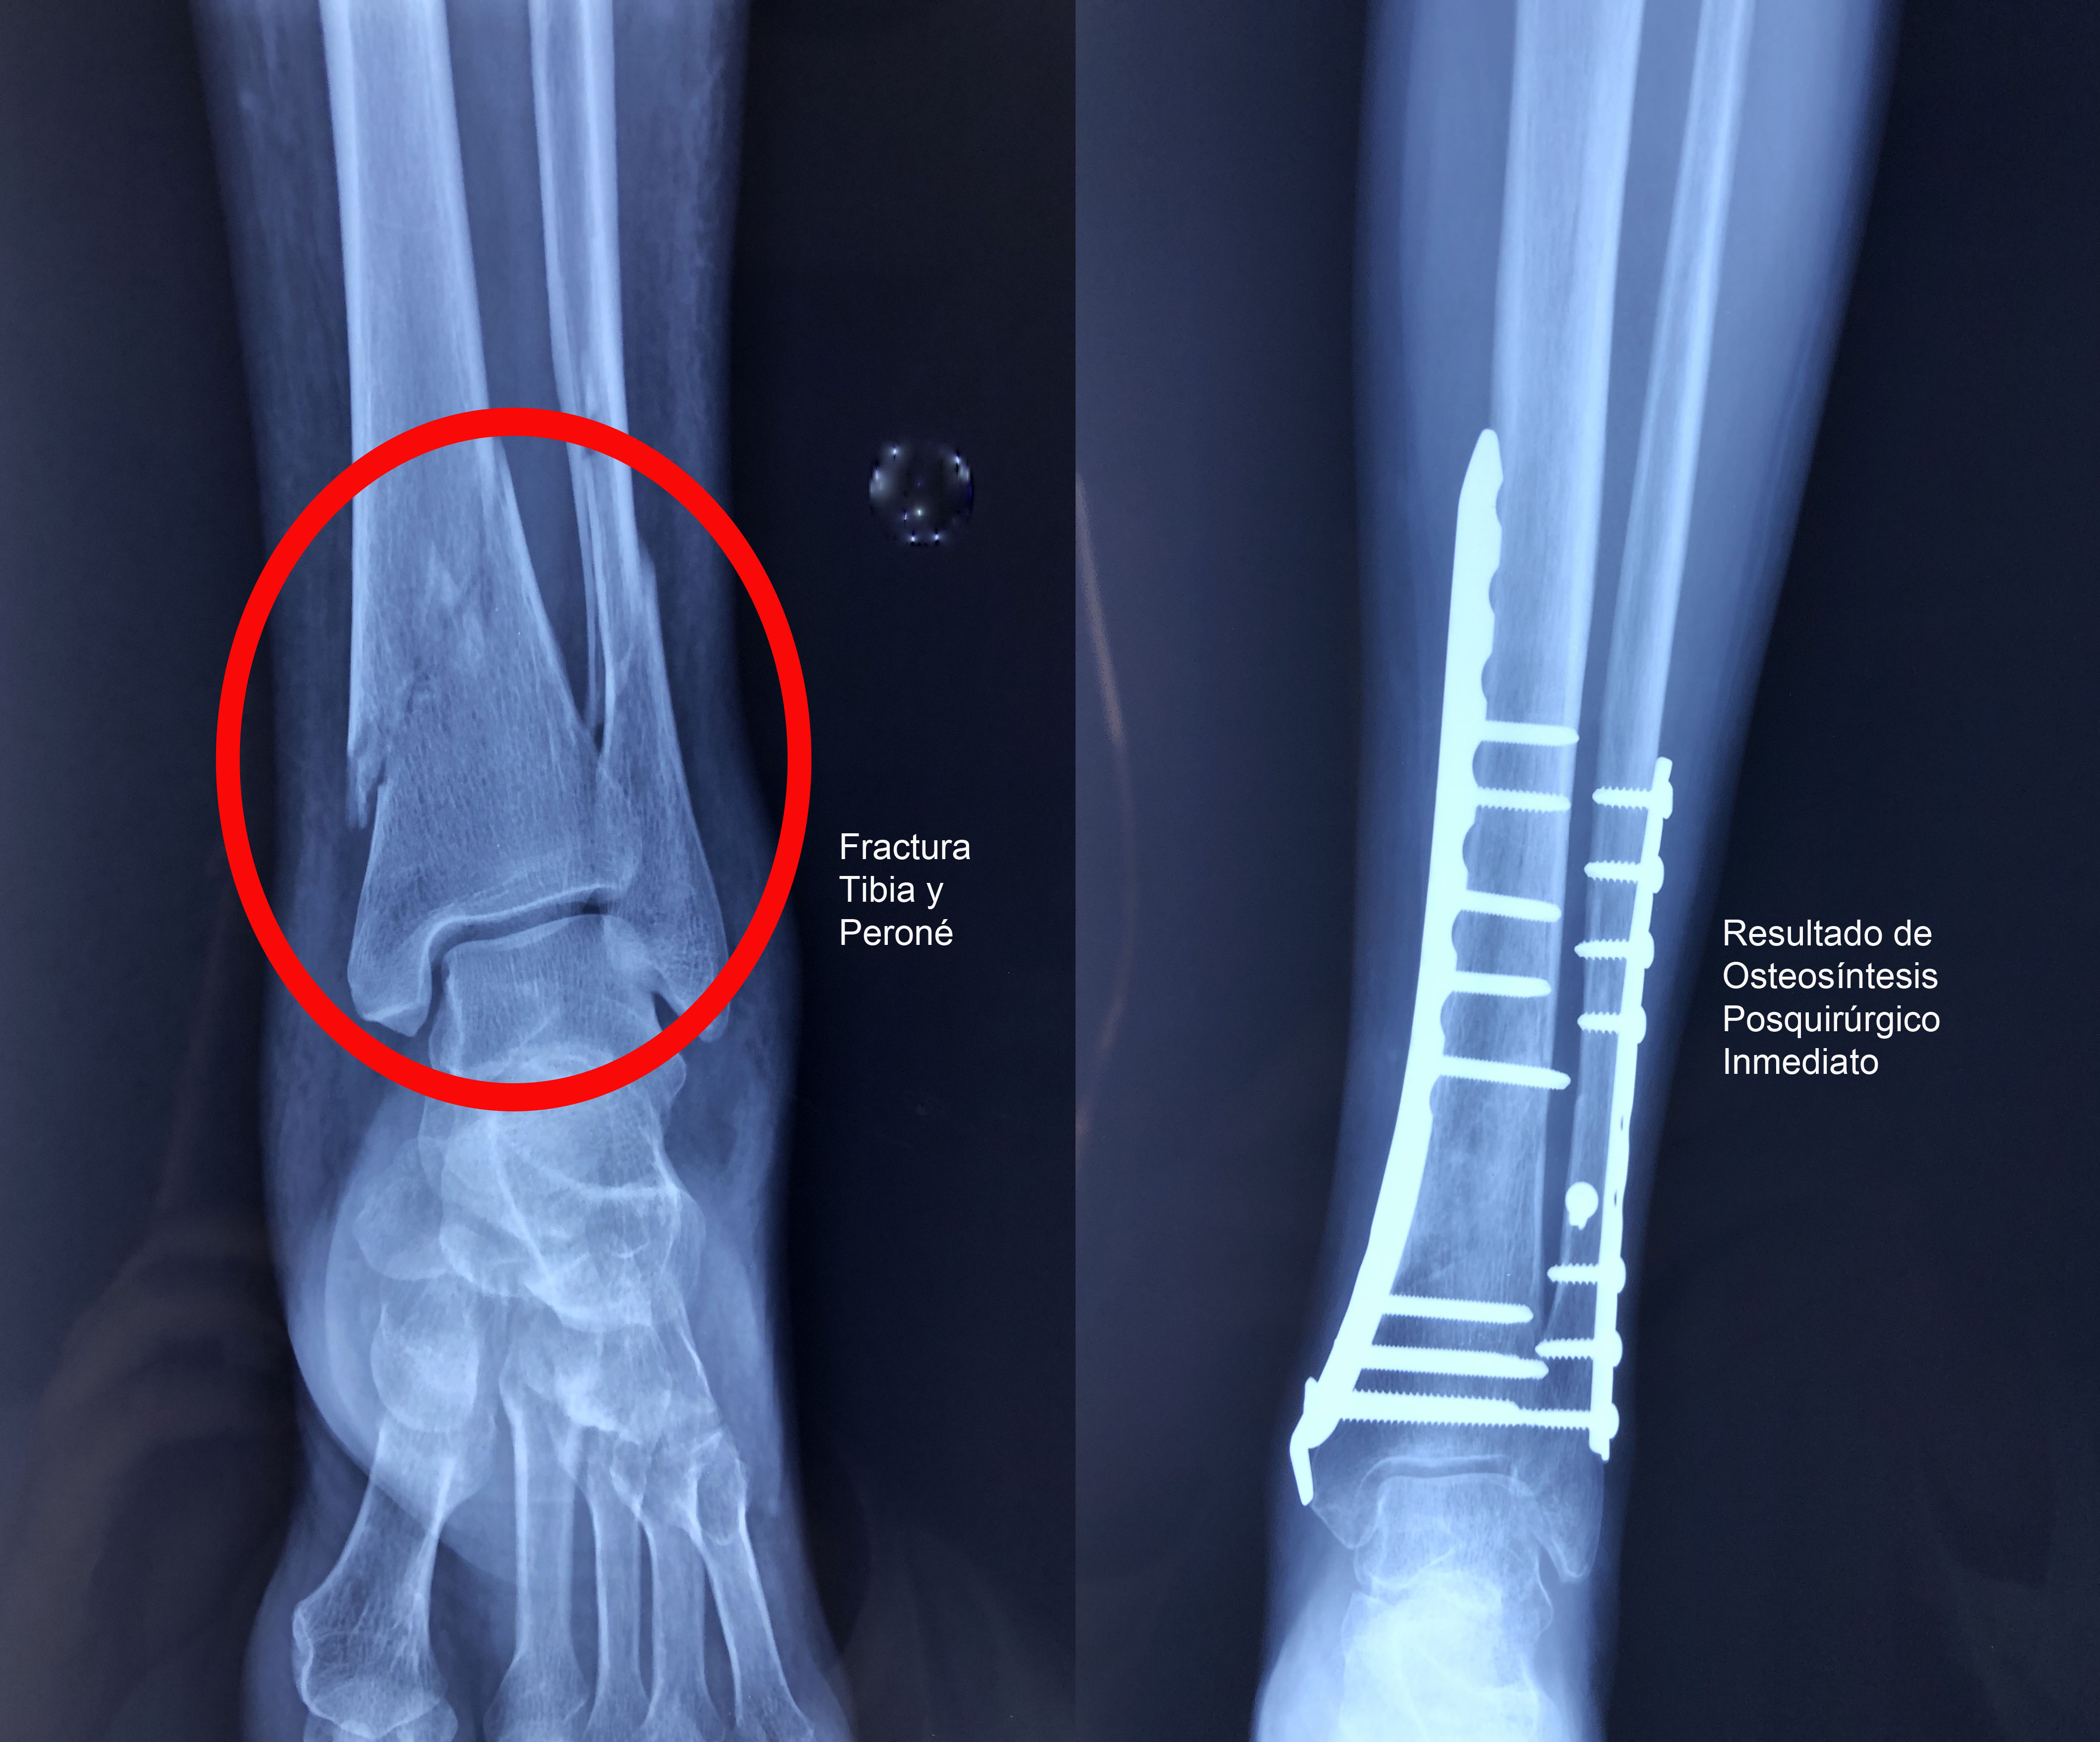

Una fractura ósea es la ruptura de un hueso, la cual puede presentarse por diversas causas y su tratamiento dependerá de la magnitud, sitio anatómico y de las enfermedades concomitantes. Algunas pueden manejarse de forma conservadora con solo inmovilización y hay otras que requieren de un tratamiento quirúrgico. A continuación, podrá ver algunos casos quirúrgicos, dando clic a la zona del cuerpo afectada.